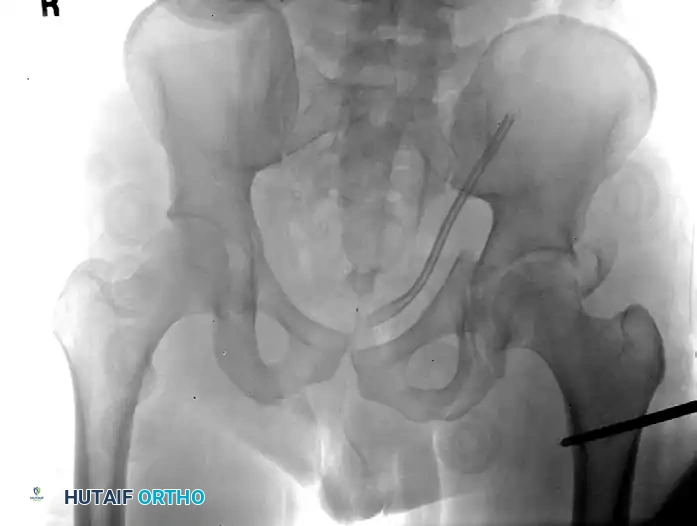

Figure 54-93 B: The proximal femur was reduced using a percutaneously positioned Schanz pin at the time of the patient’s exploratory laparotomy. The pin was subsequently incorporated into a uniplanar external fixator for temporary stabilization of the femoral fracture, dictated by the patient’s overall critical condition on presentation (Damage Control Orthopaedics).